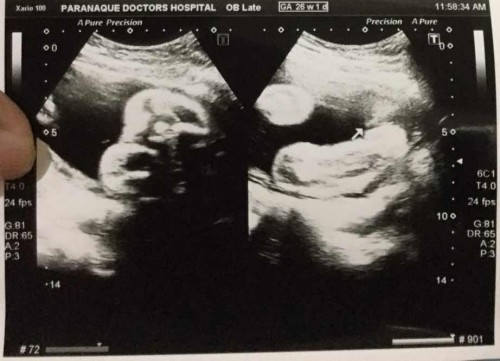

Girl or boy

Posible po bang magkamali yung nakita na gender sa ultrasound? Girl po kasi sabi ng doctor.